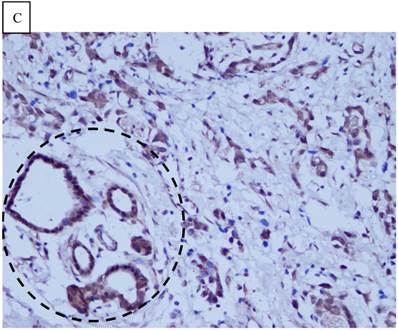

DJ-1 expression in GC was mostly cytoplasmic with some nuclear and membranous staining (Fig.1A and Fig.1B). High DJ-1 was expressed in 66.7% (76/114) of GCs. The immunostaining pattern of PTEN was also characterized by cytoplasmic and nuclear staining of the carcinoma (Fig.1C). High PTEN expression was detected in 41.2% (47/114) of carcinomas, while downregulation or loss of PTEN expression was found in most of GCs (58.7%, 67/114) (Fig.1D). Table 1 shows the correlation between markers analyzed and clinically important histopathological features of the tumors. The higher expression of DJ-1 was significantly correlated with the deeper tumor (P=0.003), lymph node metastasis (p=0.011), distant metastasis (P=0.001) and advanced clinical stage (P=0.001). However, loss expression of PTEN was only found to correlated with distant metastasis (P=0.001) and advanced clinical stage (P=0.018). Furthermore, High DJ-1 expression in tumor cells correlated negatively with downregulation or loss expression of PTEN in tumor (P=0.001).

Fig 1

Immunohistochemical staining of GC tissue microarray. (a) High expression of DJ-1 in the cytoplasm of tumor cells was shown under lower power field. (b) In some GCs, nuclear and cytoplasmic positive staining of DJ-1 in the tumor cells could be also observed. (c) High expression of PTEN could be found in tumor cells of some GCs, while, the adjacent non-neoplastic glands (circled with dotted line) showed strongly and diffusely positive staining of PTEN in cytoplasm and nuclear. (d) However, in most of GCs, PTEN expression was entirely loss or remarkably reduced. (a and d, immunohistochemical staining with original magnification ×100; b and c, immunohistochemical staining with original magnification ×400).